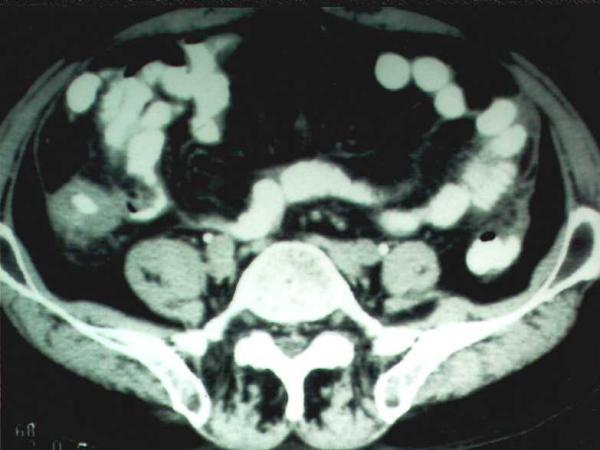

Here, we report a case of isolated colonic tuberculosis where the initial diagnostic workup was suggestive of Crohn's disease. Computed tomography findings however, raised the possibility of colonic tuberculosis and the detection of acid-fast bacilli in biopsy specimens confirmed the diagnosis.

在此,我们报告一例孤立性结肠结核病例,其初始诊断检查提示克罗恩病。然而,计算机断层扫描结果增加了结肠结核的可能性,活检标本中抗酸杆菌的检测证实了诊断。